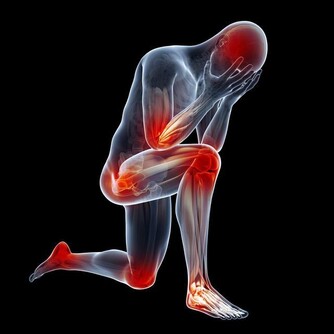

痛風的確是一種令病人非常痛苦的一種病症,當它發作的時候,可以說是「痛不欲生」,這種毛病還真會整人,它發作時間通常是選擇在夜深人靜的時刻。青木瓜泡茶加新鮮椰子汁:痛風再見了!

有著神奇的功效,對於治療中西醫束手無策的痛風,卻有令人無法想像的療效,只要早晚飲用一顆新鮮椰子水,即使痛風情況嚴重到骨關節變形,依然可以康復。 藥書泰斗嘉眾草師表示,根據統計發現,國人尿酸過高的情形日趨嚴重,而尿酸過高的患者極有會發展成痛風。 高尿酸的形成主要原因有二: 一、尿酸產生過多; 二、尿酸排泄減少。許多患者只有血清尿酸鹽濃度的增高而沒有臨床症狀,只有在發生關節炎時才稱為痛風。痛風的病理基礎是高尿酸血症,正常人血尿酸值是男性2.4-7mg/dL,女性1.6-5.2mg/dL。 當體液中尿酸濃度超過此值時,將因過剩而在組織中沈積,這種尿酸鹽的結晶沈積在關節滑膜、關節骨、軟骨而導致痛風性關節炎,沈積在皮下則形成痛風石。 中西醫均會要求痛風患者不可以攝取高普林食物,然而這些食物可以說是最起碼的美食,要痛風病患完全不吃這些食物,說真的,這種治療的犧牲代價還不小呢! 他們所提供的忌食食物包括有:雞、鴨、鵝、豬等內臟,以及魚、黃豆、發芽豆類、含酵母的飲料如養樂多、啤酒、豆苗、黃豆芽、蘆筍、紫菜、香菇、肉汁、濃肉湯、牛肉汁、雞精、酵母粉、健素糖等。 以上的食物對痛風患者來說,每一樣都必須忌口,那麼在飲食的享受上,他們都被排除在外,甚至平時可選擇的食物,必須去掉一大半以上,那麼人生還有什麼意義呢? 嘉眾草師以編著《小偏方治大病》、《草藥驗方大全》、《補酒藥酒大全》、《漢方治百病》、《癌症驗方大全》等等大部頭醫藥叢書聞名於世,他提供的驗方無不受到民眾的好評,為了對付中西醫束手無策的痛風,嘉眾草師特別介紹椰子食療法,患者只要每天飲用一至三粒新鮮椰子,一至兩個小時痛風就不再疼痛,連續飲用二至三個月,症狀即可消除。 如果沒有新鮮椰子,剝殼椰子也可以,每個約在廿至四十元之間。萬一購買不便,則改喝罐頭半天水、椰子水也可以,不過還是以新鮮椰子療效最好。 嘉眾草師表示,許多人耽心椰子會不會太涼?其實這是多慮了,因為患有痛風的人,本身體質會偏燥,高普林會不斷累積,椰子水正好可以清洗積存的痛風石,這是西藥秋水仙很難做到的。